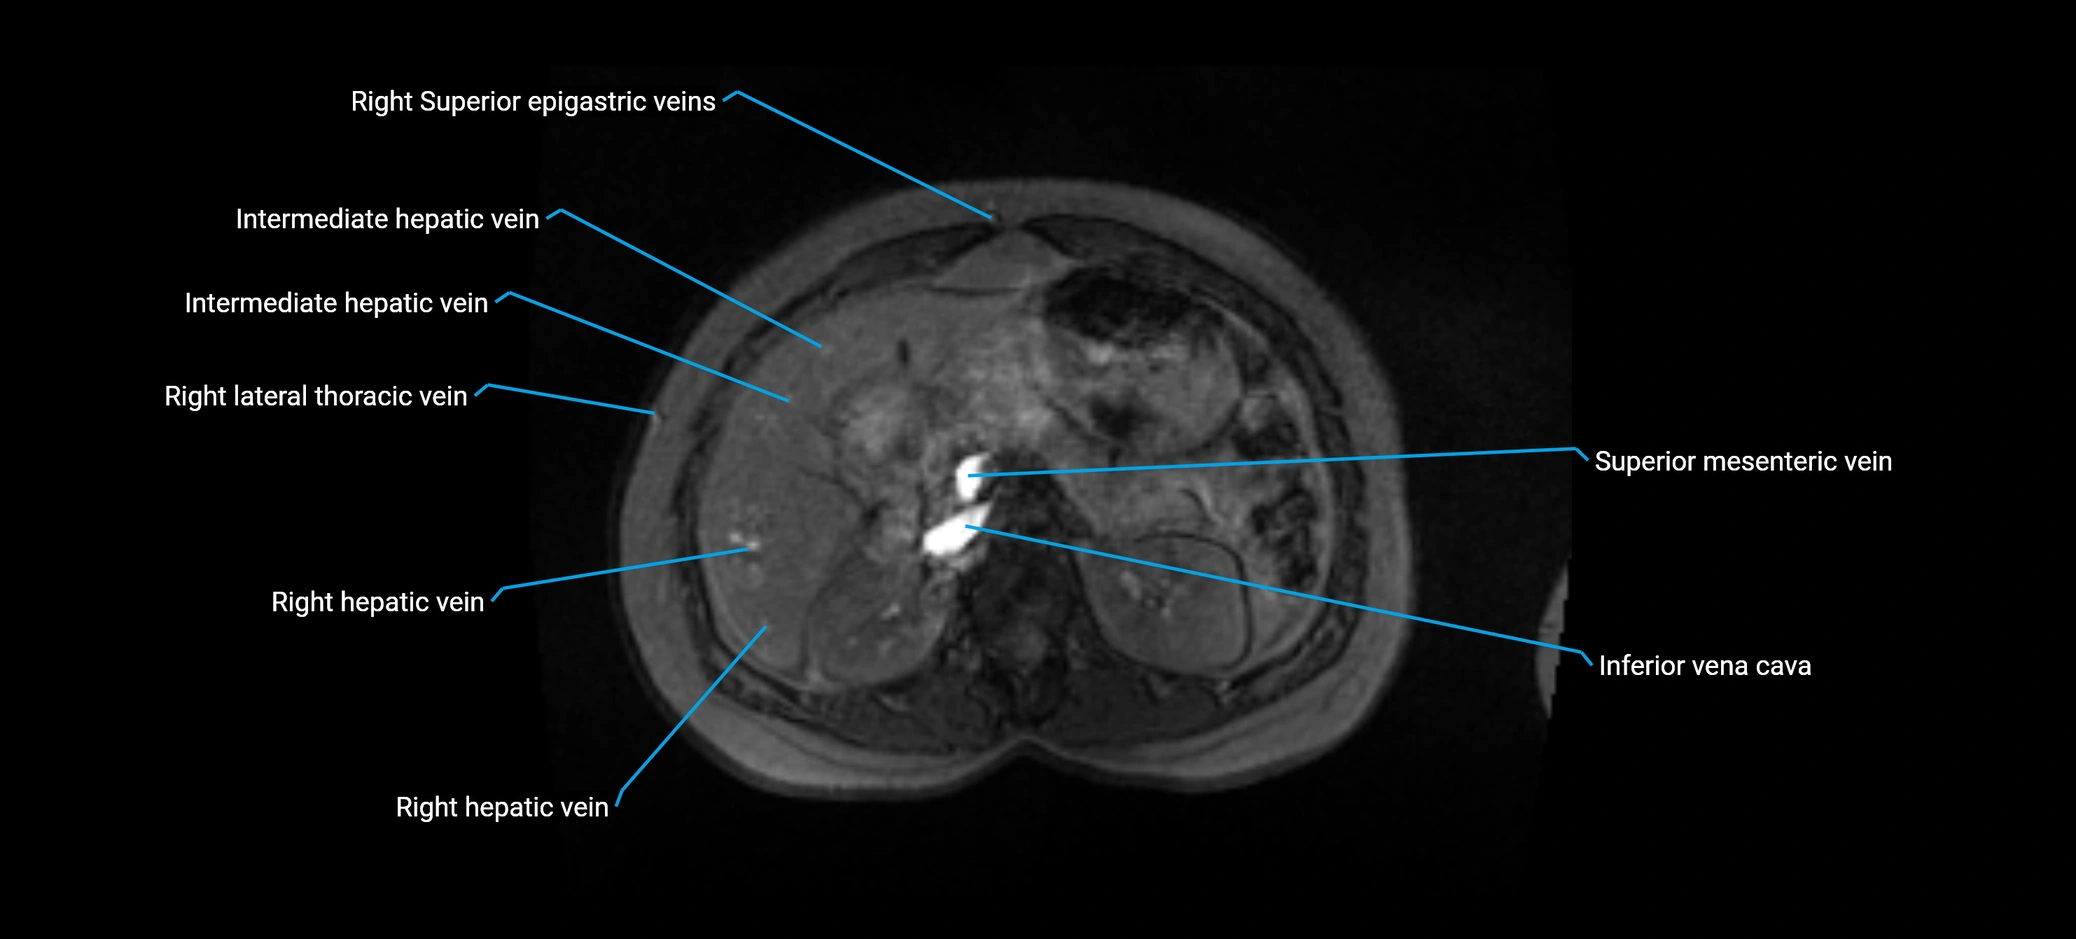

MRI Appearance

MRV TOF (Time-of-Flight MR Venography):

• Appears as a bright, high-signal vascular channel representing flowing blood

• Clearly shows branching pattern of right portal vein into anterior and posterior branches

• Best in coronal or axial reconstructions for segmental mapping

• No need for contrast, relies on flow-related enhancement

T1 Fat-Saturated GRE:

• Portal vein lumen typically dark (flow void)

• Surrounding hepatic parenchyma: intermediate signal

• Vessel wall: thin low-signal contour

• Branching course outlined by bright surrounding fat planes

T2-weighted MRI:

• Flowing blood within the anterior right portal vein appears as dark flow void

• Hepatic parenchyma appears moderately bright

• Excellent for visualizing course and anatomic relationships

• Biliary radicles appear brighter, helping vascular-ductal differentiation

Post-Contrast T1 Fat-Sat GRE:

• Enhances brightly and homogeneously during the portal venous phase

• Clearly delineates branching into segments V and VIII

• Best sequence for evaluating patency, caliber, and anatomic variants

• Early arterial phase: minimal enhancement

• Delayed phase: gradual washout but still brighter than hepatic parenchyma

MRI image

image